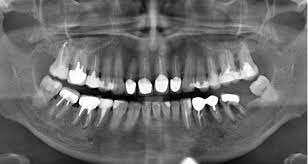

взято с общего доступа

Как «рентген» может увидеть то, что скрыто? Основой любого рентгеновского аппарата является катодная трубка, испускающая рентгеновские лучи (так их называли сами первооткрыватели). Луч проходит через тело пациента и улавливается расположенным за ним детектором: рентгеночувствительной пленкой или цифровой пластиной. Различные ткани поглощают рентгеновские лучи по-разному. Эти отличия позволяют получать изображения внутренних органов больного на кинопленку или на экран компьютера. Наиболее плотные структуры (кости) показаны на изображении белым цветом, более мягкие структуры, такие как мышцы и жир, показаны серым цветом, а воздушные карманы показаны черным цветом. Нужен ли рентген во время лечения зубов? Это зависит. Фактически визуально врач может оценить состояние только видимой наддесневой части зуба, остальные ⅔ скрыты под десной. Проблемы могут возникать не только с зубами, но и с тканями вокруг корней зубов (пародонтом) и челюстной костью. Рентгеновские снимки помогают определить, все ли в порядке с этими структурами. По этим снимкам можно диагностировать, например, пародонтит (воспаление соединительной ткани в корне зуба), абсцессы, кисты или кариес, образовавшиеся под пломбами. Перед лечением стоматолог сделает рентген, чтобы спланировать будущую операцию. И в процессе, и после - следить за тем, чтобы все было сделано правильно. Людям со здоровыми зубами и низким риском возникновения проблем рекомендуется проходить полное стоматологическое обследование каждые 2-3 года в целях профилактики. Это позволит своевременно выявить скрытые патологии, не допустить их перехода в запущенные стадии. После эндодонтического лечения (лечения каналов) лучше всего каждый год делать рентген. Но вредна ли радиация? Все зависит от дозировки. К выводам об опасности ионизирующего излучения ученые пришли, изучая последствия крупных катастроф (Хиросима, Нагасаки, Чернобыль). Но в тех случаях люди получали очень высокие дозы радиации. До сих пор нет надежных исследований, которые могли бы продемонстрировать вред малых доз, особенно используемых в медицинских целях. Очевидно, что лучевая диагностика никак не влияет на наше здоровье. Или, если это так, это не так ужасно, как это часто изображается. Но есть ли пределы радиационного облучения? есть. Согласно российскому законодательству доза облучения при проведении рентгенодиагностических процедур не должна превышать 1000 мкЗв (микрозивертов) в год. Причем это правило специально направлено на пациентов, что фактически является «перестраховкой». Например, для рентгенологов, рентгенологов и многих других профессий допустимая доза облучения в 20 раз выше — 20 000 мкЗв в год. Чтобы понять, насколько велики или малы эти цифры, приведем конкретные примеры: ► Мы подвергаемся воздействию около 3000 мкЗв в год от естественных источников радиации (космические лучи и радон, выделяемый из почвы). Хотя естественные уровни радиации сильно различаются по географическим регионам. Где-то она может быть в 200 раз выше средней. ► Доза облучения при трансатлантическом перелете составляет 80 мкЗв. ► Доза облучения при маммографии (маммографии) - 400 мкЗв. Каково количество «рентгеновского» излучения в зубах? Сколько фотографий можно сделать во время лечения? В стоматологии существует несколько видов рентгенологических исследований, но все они дают небольшое количество радиации. Например, цифровая рентгенография (снимки зубов) имеет экспозицию 1–3 мкЗв. Пациенты получили дозы 13-17 мкЗв при цифровой ортотомографии и 25-30 мкЗв при пленочной. Компьютерная томография (КТ) зубных рядов дала нагрузку 45-60 мкЗв. В зависимости от допустимой дозы облучения пациенты могут пройти до 500 рентгенограмм, 80 цифровых ортотомограмм и 20 КТ в год. Частота рентгенографии определяется врачом. При необходимости рентген можно делать несколько раз в день. В любом случае доза облучения, которую он получит, невелика. Обычно он в десять раз меньше, чем рентген любого другого органа (просто потому, что другие органы больше по размеру, чем зубы). А как же рак и лучевая болезнь? Я уверен, что не заболею? О лучевой болезни можно говорить при дозах облучения выше 0,7 Зв, или 700 000 мкЗв. При дозах выше 100 000 мкЗв значительно увеличивался риск неопластического заболевания. Даже если сложить дозы облучения от естественных источников и дозы от медицинских осмотров, число все равно будет меньше. Поэтому о проблемах со здоровьем можно не беспокоиться. Говорят, красное вино защищает от радиации. 2. Можно ли его пить после рентгена? Очевидно, это миф. Ни в одном справочнике по радиационной защите не рекомендуется пить красное вино или любой другой алкоголь. Поэтому пациент сам решает, что пить, когда пить и сколько пить.